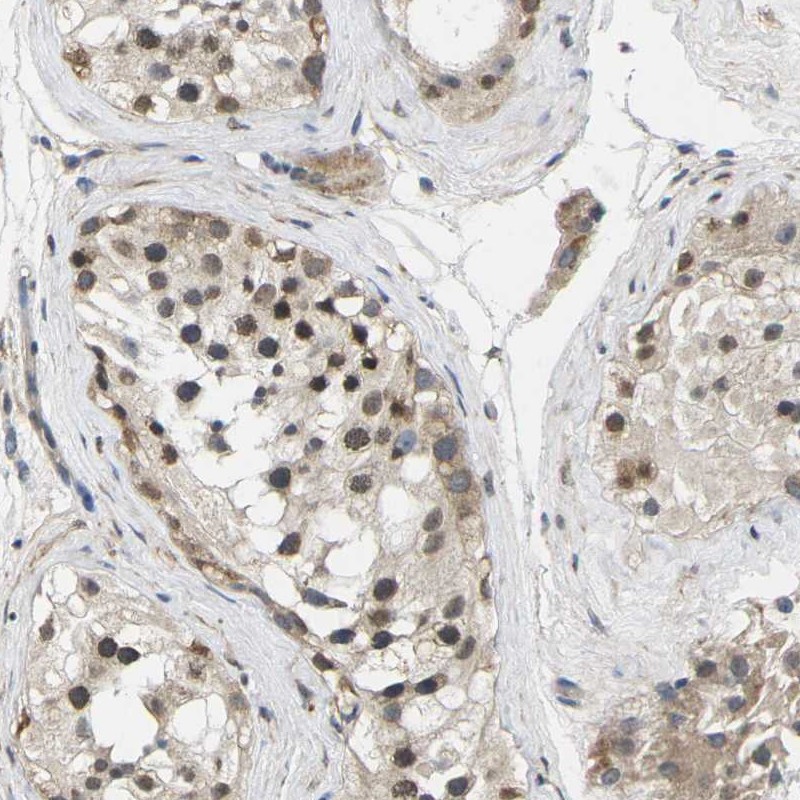

Immunohistochemistry analysis in human testis and liver tissues using Anti-ERBB4 antibody. Corresponding ERBB4 RNA-seq data are presented for the same tissues.